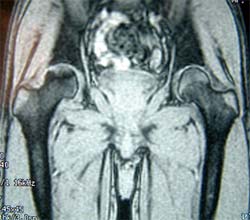

股骨头缺血性坏死MRI显示坏死区 微创手术方法,刮除死骨